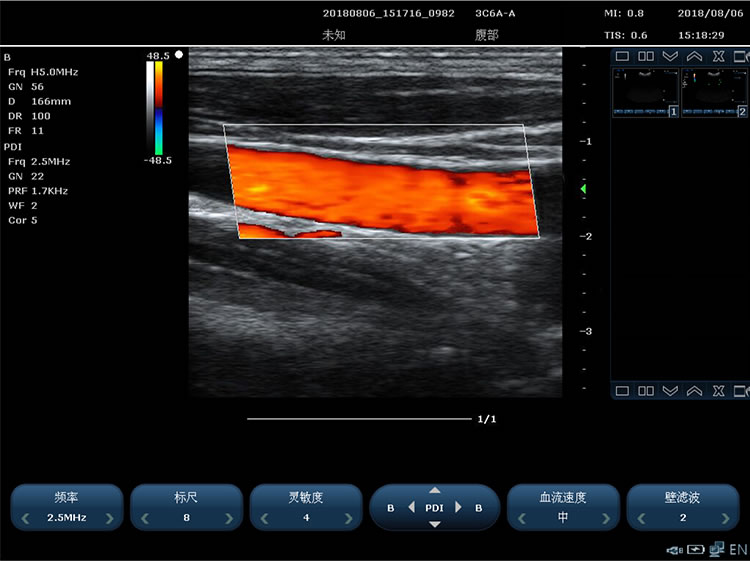

3)能量多普勒成像 4)PHI脉冲反相组织谐波成像+频率复合技术

1)成像模式包括:B 模式、2B模式、4B模式,M模式、Color(彩色多谱勒)模式、PDI(能量多普勒)模 式、PW 模式、CW 模式、解剖M、B+C+PW 三工、B+PDI+PW 三工、支持单窗口显示, 双窗口实时显示,四窗口显示

12.彩色多普勒技术要求:

1)多普勒增益连续可调 2)彩色增强功能

3)具备同屏左右双幅同时显示 B+COLOR 功能 4)彩色模式基线调节±15 级